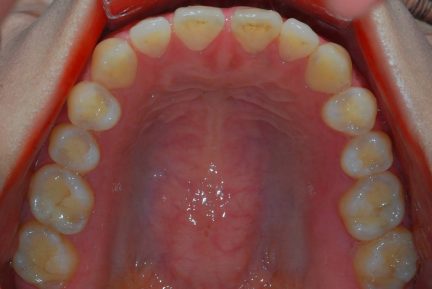

Classe III, articulé postérieur, arcades étroites, arcades asymétriques, déviation de la ligne médiane mandibulaire, décalage de la ligne médiane, rotations, espacement

État initial